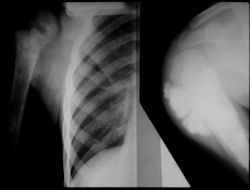

Radiographic Presentation: Conventional Osteosarcoma

There are 3 radiographic presentations for osteosarcomas, depending upon the amount of osteoid/ossification and calcium deposition:

- Mixed sclerotic and lytic, permeative lesion most common radiographic presentation

- Purely osteoblastic, permeative lesion: dense sclerosis and osteoid production

- Purely lytic, permeative lesion: little osteoid production and/or minimal calcium deposition in osteoid

Conventional osteosarcomas are permeative lesions on plain radiographs (borders of the lesion cannot be clearly delineated)

- Wide zone of transition from lytic/sclerotic areas of tumor to normal bone

- Makes borders of lesion hard to define

- Most (90%) arise from the metaphysis of the bone

- Rarely (10%) arise from the diaphysis

- Most conventional osteosarcomas (90-95%) extend through the bone into the soft tissues and form a soft tissue mass outside of the bone